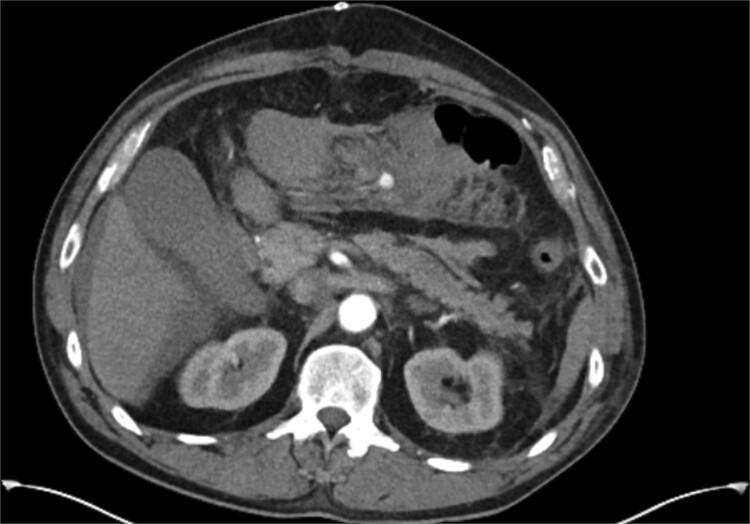

We present the first published account of a pseudoaneurysm of the Marginal artery of Drummond (MAoD) following an emergency open surgical repair of an inflammatory abdominal aortic aneurysm, in which the inferior mesenteric artery was ligated. This was hypothesized to be an iatrogenic injury secondary to retraction of the colonic mesentery during dissection of the aneurysm neck. The risk of pseudoaneurysm growth and rupture versus bowel ischaemia were evaluated in the post-operative phase. Ultimately, the patient underwent successful interventional embolization of the MAoD with no signs of bowel ischaemia post-intervention.

我们首次发表了关于在紧急开放性手术修复炎症性腹主动脉瘤并结扎肠系膜下动脉后,发生的德拉蒙德边缘动脉(MAoD)假性动脉瘤的病例报告。据推测,这是由于在动脉瘤颈部解剖过程中结肠系膜回缩导致的医源性损伤。在术后阶段评估了假性动脉瘤生长和破裂与肠缺血的风险。最终,患者成功接受了MAoD介入栓塞治疗,术后无肠缺血迹象。